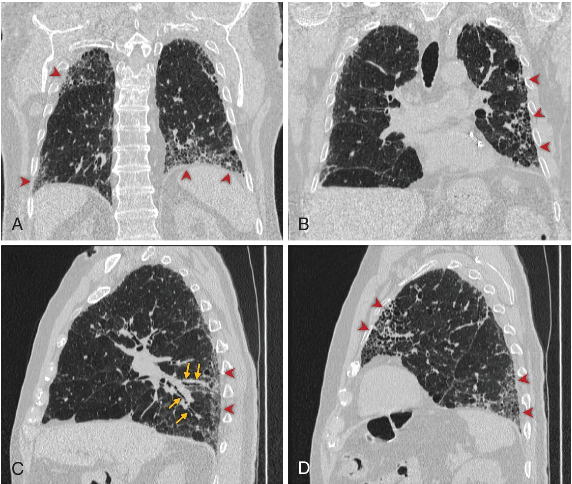

La tomografía computarizada de alta resolución (TCAR) es esencial para identificar la presencia y el tipo de enfermedad pulmonar intersticial. En la FPI, el patrón radiológico más frecuente es el de neumonía intersticial usual (NIU), asociado a un peor pronóstico. Su identificación se basa en tres hallazgos clave:

- Panal de abejas: espacios aéreos quísticos subpleurales con paredes definidas.

- Bronquiectasias por tracción: dilatación bronquial secundaria a distorsión del parénquima.

- Predominio subpleural y basal de las reticulaciones y del panal de abejas.

La presencia de crepitantes finos basales llevó a solicitar una TCAR, que mostró reticulaciones periféricas, bronquiectasias por tracción y panal de abejas de predominio basal, compatible con un patrón NIU. Las pruebas de función pulmonar revelaron un patrón restrictivo con disminución moderada de la capacidad de difusión de monóxido de carbono. Los estudios reumatológicos fueron negativos, descartando una enfermedad del tejido conectivo. El caso fue revisado por un equipo multidisciplinario compuesto por neumólogos, radiólogos y reumatólogos.